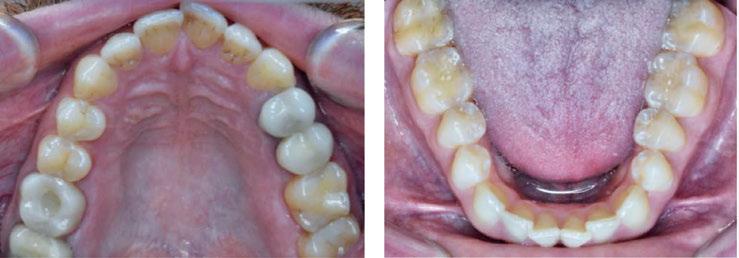

An OMD assessment with TMD muscle pain: a case study

Judith Dember-Paige, BSOHP, COM®, discusses how transformation sometimes takes years, but it’s worth the effort

Stan was referred to my office by a TMD specialist. His chief complaints were he could not chew or open his mouth without pain. It seemed the less he chewed, the more pain he experienced. As a result, an Orofacial Myofunctional Therapy (OMT) program was created to help support his muscles of the TMJ and craniofacial respiratory complex. He used his splint as instructed by his specialist. However, his anterior open bite widened, and his teeth became more misaligned over time.

Upon closer examination, there were contributing factors that led to his discomfort. Stan had been a stomach/face sleeper for years. He also bit his nails since childhood, had a smoking habit from his youth, and he was prone to ear infections. He had moderate tongue and buccal ties, obligate mouth breathing, aggravated by a deviated septum, narrow nares, low tongue resting posture, an anterior open bite, a lower jaw that deviated upon opening, and bouts of acid reflux.

When the tongue rests in the palate, it impacts facial development especially for children who are still growing. An adult, for example, like our friend Stan, the progress made is gradual but more likely to last a lifetime. Generally, therapy starts out once a week for about 2-3 months. Then therapy progresses to every other week for 2-3 months, and then changes to once a month for about 5 months for the rest of the year. The exercises are done a minimum of 2 times everyday. These exercises are designed to strengthen and tone the orofacial muscles, building brand new neuromuscular function. When the muscles of the face are well developed, it may favorably impact appearance and the overall integrity of the facial structures. The muscles of the face also include the tongue, lips, cheeks and neck. Although the therapy program is typically only a year, Stan really liked how good he felt and decided to continue with some of the exercises to this day. From the photos you can see how much the program has impacted his health and well-being.

During his therapy, there was a discussion about the possible benefits he may receive from having his jaws expanded, making more room for his tongue, then to be followed by a tongue and buccal frenums release. His intermolar width is 34 mm, and his intercanine width is 25 mm. I feel any expansion has a potential benefit.

To document any initial assessment, the midpoint of therapy, and when therapy has ended, it is important to take detailed photos, videos, plus full measurements of the face and teeth. This makes it possible to compare results while showing that your therapy works based on the evidence you gathered before, during, and after treatment.

Figure 5

Figure 6: No room for his tongue

Figure 4: 7 years later on April 10, 2024. Anterior open bite closed a bit

Figure 2: Initial assessment on December 15, 2016 (top left). Later September 20, 2017, his anterior openbite widened (top right)

Figure 3: Milled orthotic splint